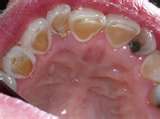

Soft Drinks and Tooth Decay

Most people are aware that soft drinks contain sugar and/or sugar substitutes. However, are you aware of the amount of 'acid' in the soda you drink? Even diet sodas are acidic in nature, therefore they can still weaken tooth enamel. Several popular soft drinks were tested for their sugar and acidity. In a 12 oz serving results show a range from zero to ten teaspoons of sugar and from 2.53 to 4.61 pH with a pH of 7 being neutral. Also, don't be misled in thinking soft drinks are the only culprits. Many 'ready to drink' iced tea, lemonade, juice and energy drinks are just as damaging to your teeth. The key is to drink in moderation or even better......drink water instead.